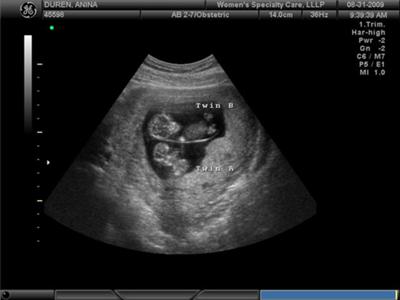

Разумеется, точно пересчитать малышей в вашем животе сможет только врач во время УЗИ (сделать его можно уже на 4–5-й неделе беременности).

Благодаря современным методам диагностики, многоплодная беременность определяется еще на ранних сроках. Во-первых, врач может диагностировать двойню при обычном осмотре – обратив внимание на быстрое увеличение размера матки или услышав двойное сердцебиение. Опытный специалист может диагностировать двойню уже после 4 недель беременности. Во-вторых, двойня диагностируется при УЗИ-осмотре. Обычно это происходит после 12 недель. До этого будущая мать может только предполагать, что носит двойню – например, опираясь на семейную историю и частые случаи рождения близнецов в семье. Анализы крови достоверным способом определить двойню пока не являются.

Однако подтвердить, что у вас будет двойня, сможет только врач. Чаще всего это бывает заметно на УЗИ на 12-й неделе беременности. Если вы недавно узнали о том, что ждете близнецов, рекомендуем прочитать статью c советами при многоплодной беременности.

Иногда на шестой неделе беременности при трансвагинальном УЗИ можно зафиксировать биение сердца (или даже двух!). Тем не менее с какой-либо точностью о присутствии второго ребенка можно будет говорить только после УЗИ на 12-й неделе.

При этом у плодов имеется одна общая плацента и собственное околоплодное пространство. Плоды всегда одного пола и полностью генетически идентичны. Наличие единой плаценты может приводить к развитию специфических осложнений, связанных с тем, что сосуды в этой плаценте могут соединять системы кровообращения обоих плодов. При этом один плод получает некоторое количество крови от другого плода, и они оба страдают от этого: у одного есть избыток крови, что приводит к повышенной нагрузке на его сердце; второй получает недостаточное количество крови, кислорода и питательных веществ, и начинает расти медленнее, в результате чего у него формируется задержка внутриутробного развития. Такое осложнение называется фето-фетальный трансфузионный синдром, и без своевременного лечения может привести к гибели одного или обоих плодов. Для того, чтобы не пропустить это осложнение, необходимо делать УЗИ в 11-13 недель (как при одноплодной беременности), в 16, 18, 20, 22, 24, 26, 28 недель беременности. Если выявляются признаки фето-фетального синдрома, УЗИ нужно выполнять еще чаще – 1 раз в неделю.

Монохориальная моноамниотическая двойня — возникает при разделении оплодотворенной яйцеклетки на две части, при этом у плодов имеется общая плацента и общее околоплодное пространство. Плоды всегда одного пола и полностью генетически идентичны. Это крайне редкий тип двоен, и сопровождается самым большим риском осложнений, задержки развития и внутриутробной гибели. Помимо осложнений, связанных с единой плацентой (см. описание выше), плоды находятся в общем околоплодном пространстве и не разделены амниотической оболочкой. Это может привести к перекруту и пережатию их пуповин, прекращению поступления крови к одному из них и, соответственно, его гибели. Риск этого осложнения очень велик, поэтому УЗИ делается каждую неделю беременности, а при выявлении признаков перекрута пуповины рекомендуется госпитализация и ежедневное наблюдение плодов; если состояние одного из плодов становится критическим, требуется немедленное родоразрешение путем операции кесарева сечения.

Для диагностики различных состояний, врачи часто используют УЗИ. Будущей маме предстоит регулярно проходить такое обследование. Именно этот метод позволит узнать, сколько малышей находится в матке. Стоит выяснить, когда можно определить двойню по УЗИ. Специалист может увидеть количество эмбрионов примерно в 5-6 недель. Но по разным причинам на маленьком сроке устанавливают, что в матке несколько плодов, не всегда. В ряде случаев врач точно диагностирует этот факт позже, например, во время скрининга в первом триместре.

Самый точный способ подтвердить то, что у вас многоплодная беременность — узи диагностика. Этот метод позволяет на ранних сроках определить количество зародышей с точностью 99,3%.

С большой вероятностью двойня на УЗИ заметна после 5-ти недель, если совершается передвижение зародыша по направлению к матке и визуализируется два черных пятнышка. Обследование по УЗИ назначает личный гинеколог, если сможет заметить активный рост объемов матки. Чтобы узнать про наличие монозиготных плодов УЗД визуализирует их не ранее 12 месяцев. В данный промежуток времени у зародышей разделились пальчики на обеих руках, сформировывались пуповины и развивается 1, 2 плаценты. Исследование происходят систематически (ежемесячно) для своевременного распознавания присутствия/отсутствия патологий. Увидеть развитие двух плодов согласно диагностике на ранних сроках весьма затруднительно из-за специфик положения и особенностей УЗД техники (новейшие устройства имеют наиболее высокие возможности к точному осмотру).

Женщины с многоплодной беременностью должны быть под постоянным присмотром. Определить многоплодную беременность можно на УЗИ, также как при обычной беременности. На сроке в 5 недель на УЗИ можно увидеть, сколько малышей родится.